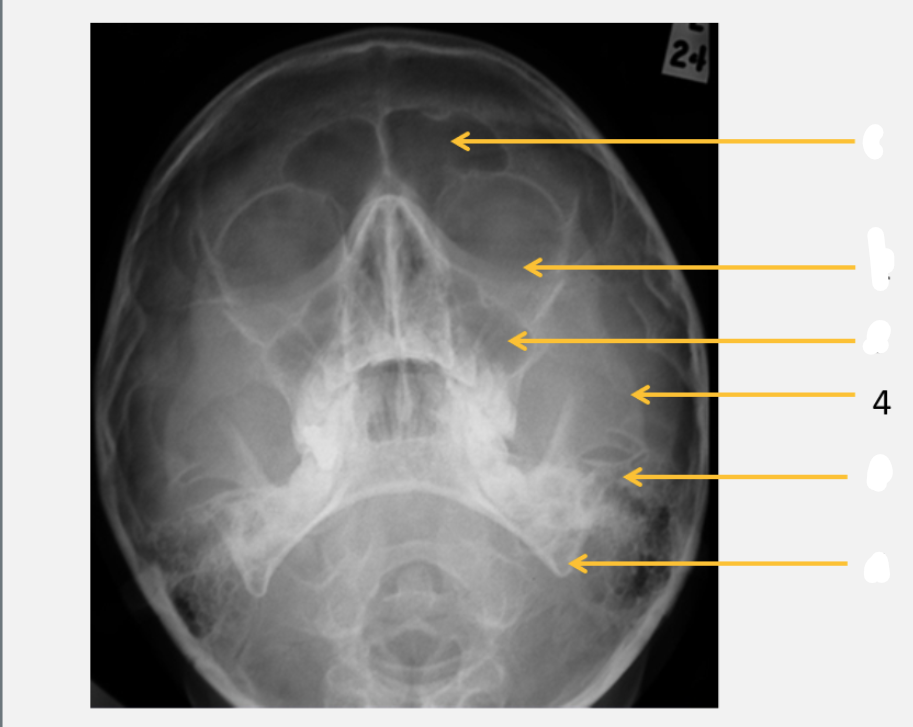

frontal bone

frontal sinus

parietal bone

lambdoid suture

occipital bone

mastoid air cells

Sella turcica

inferior orbital rim

maxillary sinus

zygomatic arch

petrous ridge

angle of mandible